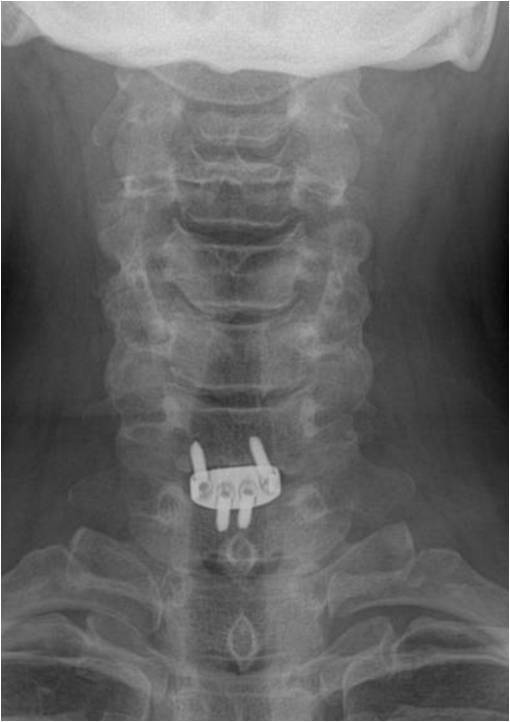

颈椎病产生的病理因素是椎间盘,无论是神经根型、还是脊髓型颈椎病。因椎间盘退变可导致脊髓、神经根等受压,亦可形成后方骨赘。那么处理该问题时,就不应该切除椎体,而应该以针对性椎间隙减压即可。所以,张教授在行颈前路手术时,均以单间隙减压充分为目的。无一例行椎体次全切手术。他强调:如有可能,尽量进行单节段固定、融合,强调零切迹的Zero-P的使用。这样,稳定程度高。

Zero-P融合固定 |

常规开展,最为推崇 |

省内率先开展(包括腰椎),医保、费用限制 |